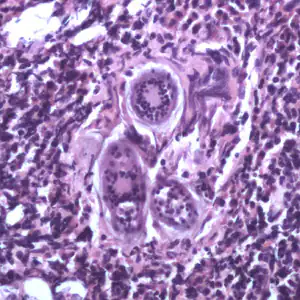

Schistosoma spp. eggs in tissue, stained with hematoxylin and eosin (H&E).

Cross-sections of human tissues with Schistosoma spp. adults.